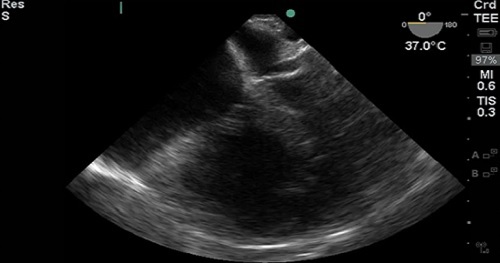

Description

- Superior Vena Cava (SVC)

- Right Atrium (RA)

- Inferior Vena Cava (IVC)

- Left Atrium (LA)

- Interatrial Septum